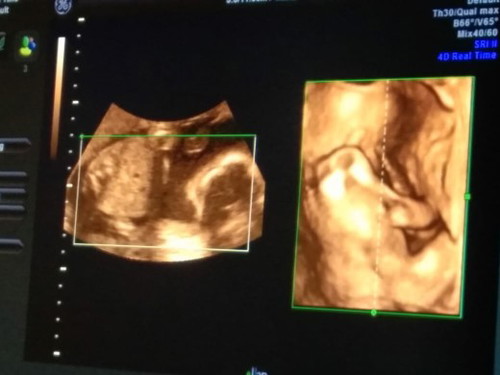

usg 4d

bun mau tanya saya kmren usg 4d usia kandungan 20 minggu 4 hari,,cuma prediksi dr cantik,,nah itu dokter udh terkenal gk meleset kebnyakn orang,,klo usia kandungan 5 bulan masih bisa kah berubah ya bun

Tu dia gk nunjukin jenis kelamin nya bun,,cuma prediksi..bayi ku ngebelakangin bun